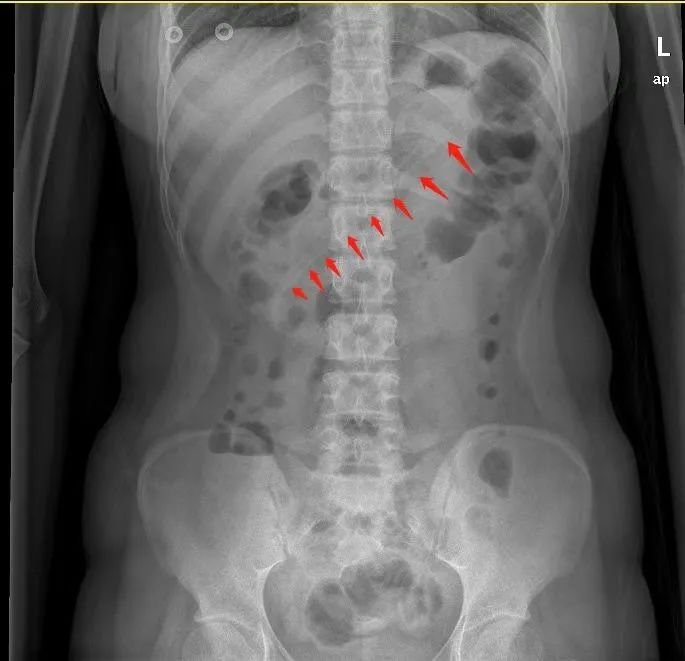

该院普外科负责人称,该患者是一名中年男性,因右侧腹痛难忍,腹痛长达3个月,无奈来到医院就诊。经腹部CT检查,提示其升结肠占位,淋巴结肿大。医生初步考虑患者可能是回盲部患有肿瘤。

李小姐去东莞石碣医院求助医生,腹部X线检查显示,李小姐胃中的勺子长达17厘米。如果不取出,患者可能会出现消化道梗阻、出血和穿孔等并发症。医生赶紧安排李小姐入院治疗。